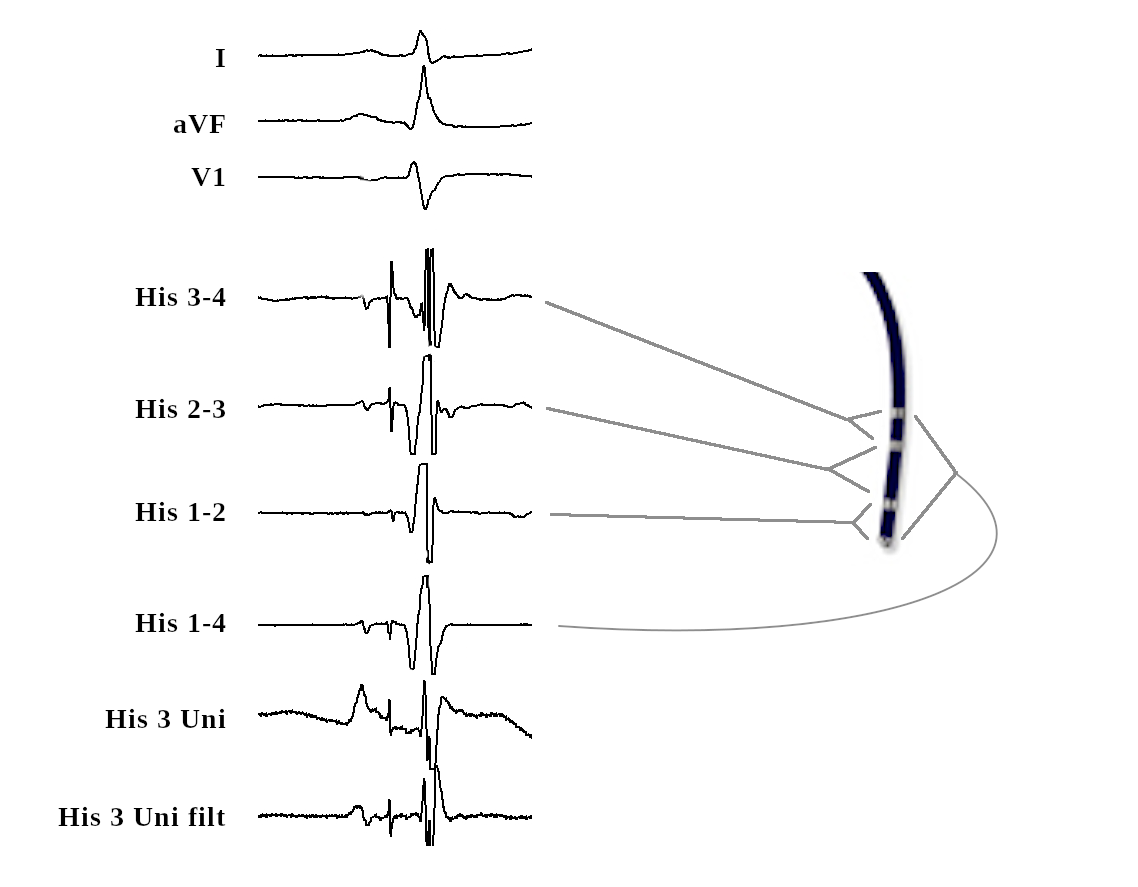

His

• Deflectable quadripolar catheter

• 2-5-2 spacing

• Should record atrial signal

Filtered Unipolar

• Far field lower frequency signal

• High pass filter (30Hz) reduces far field component

his_signals.png